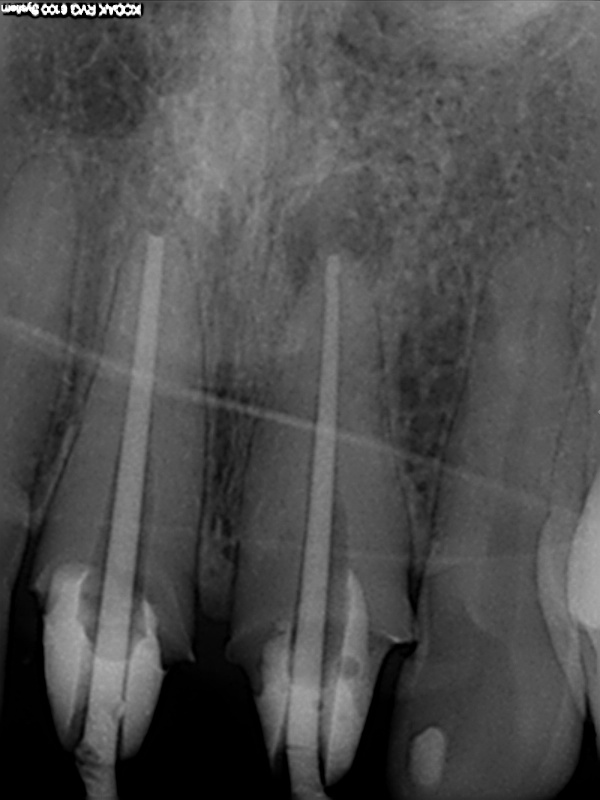

und wieder ein Recall

Messaufnahme